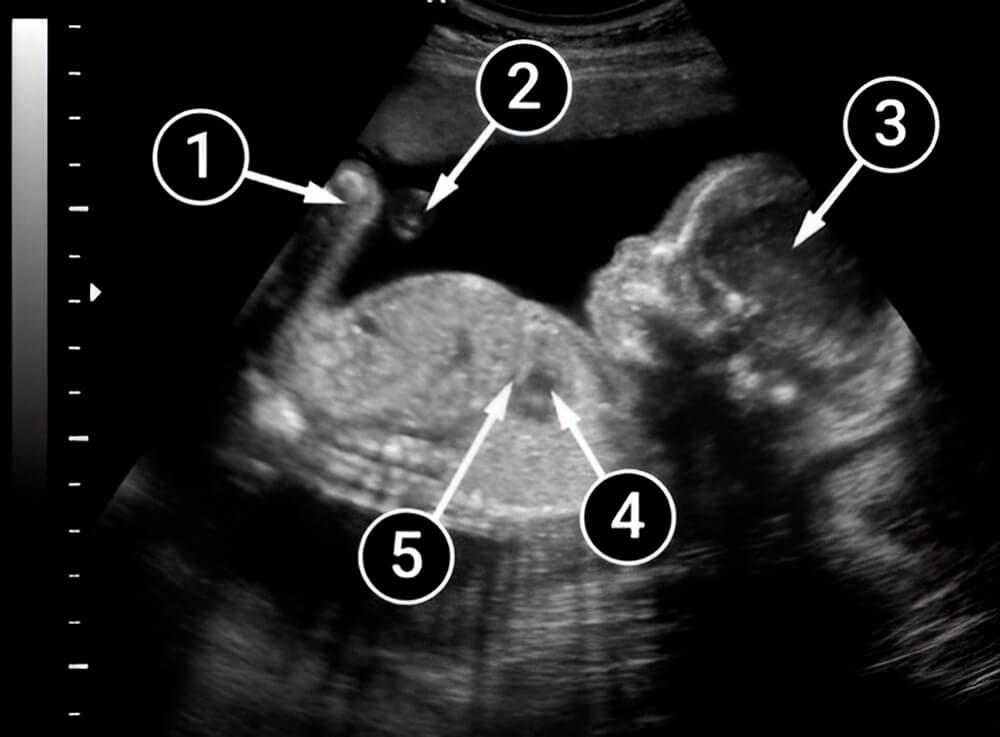

Lo que podemos ver en un ultrasonido

El bebé está boca arriba con el lado izquierdo volteado hacia la pantalla. Los contornos de la cabeza y el cuello son visibles y la frente, la nariz y los labios están claramente definidos. El área oscura alrededor del pecho es el corazón del bebé. En la imagen también se puede ver el diafragma, una delgada línea que separa el pecho y la cavidad abdominal.

La imagen muestra claramente el vientre redondeado y las piernas del bebé. También se ve el cordón umbilical, que transporta nutrientes del cuerpo de la madre al bebé.